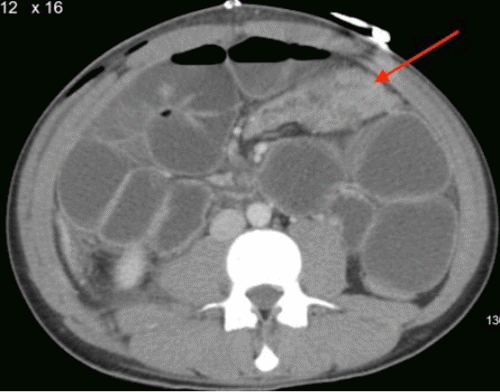

Contrast-enhanced CT scan of the abdomen and pelvis revealed findings consistent with mechanical obstruction. A transition point abutting the abdominal wall at the prior projectile injury site was noted proximal to the ileocolic anastomosis (Figure 3). A small bowel follow-through demonstrated small amounts of contrast in the distal small bowel loops at an 8-hour delay, indicating possible incomplete obstruction (Figure 4). Following discussion with the patient and guardian, a decision was made to perform a re-exploratory laparotomy.

Figure 3. CT Depicting Mechanical Small Bowel Obstruction at Prior Injury Site. Published with Permission

Axial view demonstrating the transition point abutting the fascial defect in the abdominal wall